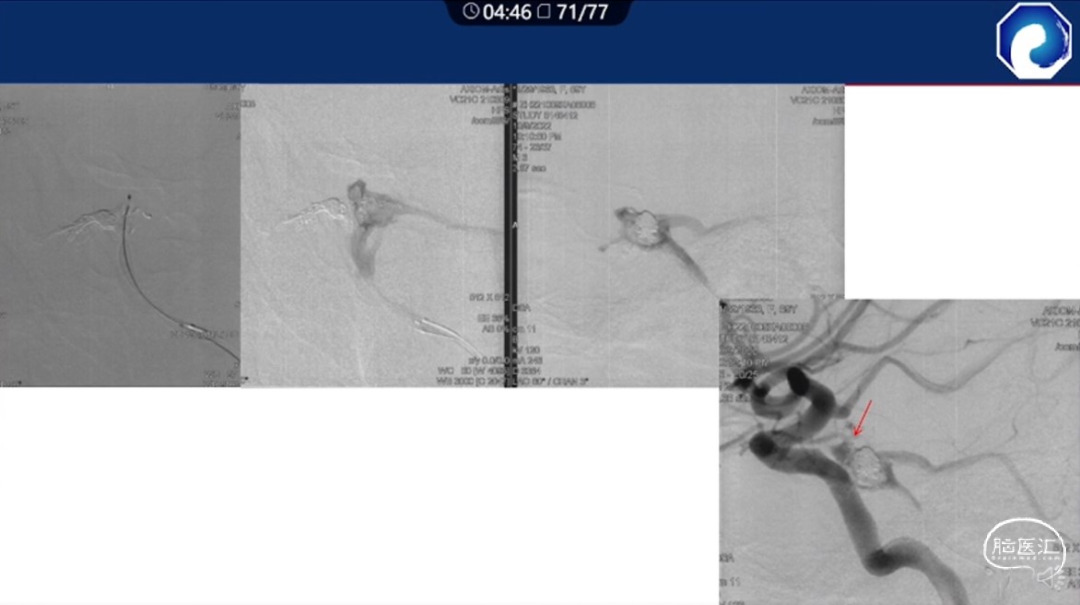

痿口静脉端精准完全闭塞是DAVF治愈的关键。

靶向性栓塞可以减少海绵窦分隔的过渡栓塞,有利于减少颅神经并发症,恢复海绵窦的正常引流功能。

减少栓塞材料应用。

减少与颈内动脉重叠,避免栓塞材料意外栓塞。